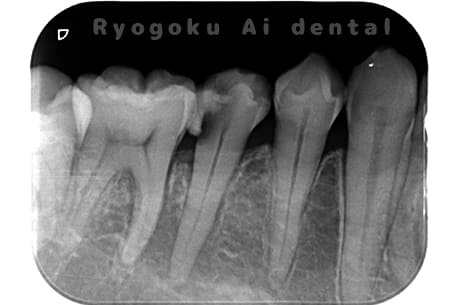

Case05

-

- 原因

- 慢性根尖性歯周炎

- 治療内容

- マイクロエンド

- 治療費用

- 121,000円(被せ物は含まない)

他院ではお薬の交換と抗生剤の処方で経過を診ていた患者さんです。歯茎の腫れが治らないとのことで、根管治療を開始し、2回目のご来院で腫れが引いたケースです。現在は被せ物も入り、良好に経過しております。

<リスク・副作用>

術後は痛み、腫れ、痺れなどの副作用が生じる場合があります。症状が再発する可能性があります。